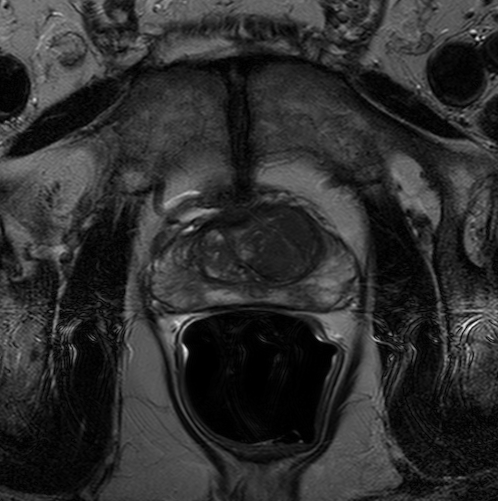

We trained our network on 77 patients. The input images and the manual ground truth annotation are shown in Fig.4. As we have described above, these images were acquired from different patients, and these images include the clinical variability. To evaluate our method, we randomly selected 4 patients with 64 images before training. These images do not take part in training and the prostate has been manually pre-delineated by a radiologist, which were used as the ground truth to evaluate the performance of automatic segmentation. We also selected dice coefficient as the evaluation method[30]. And to validate our method against U-Net and fully convolutional networks (FCNs), we used the same dataset to train and test the U-Net and FCNs.